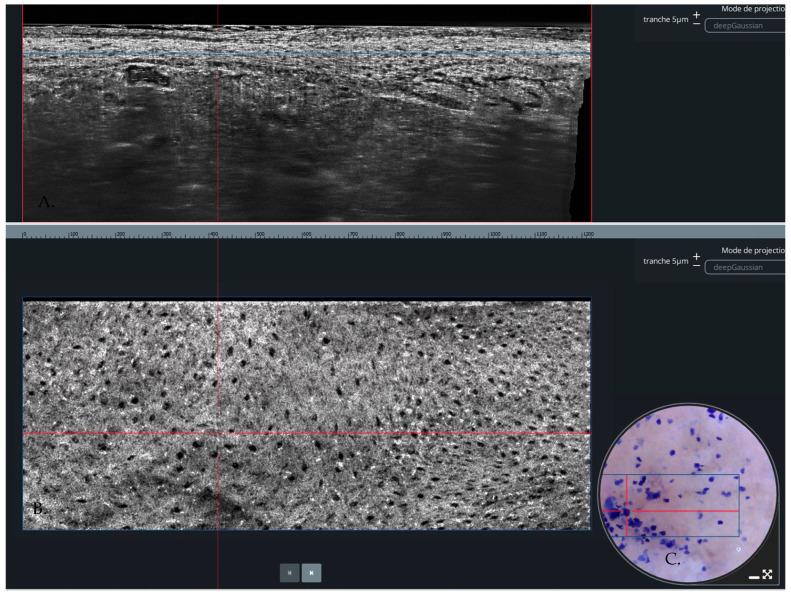

A line-field confocal optical coherence tomography (LC-OCT) combines confocal microscopy and optical coherence tomography into a single, rapid, easy-to-use device. This meta-analysis was performed to determine the reliability of LC-OCT for diagnosing malignant skin tumors. PubMed, EMBASE, Web of Science databases, and the Cochrane Library were searched for research studies in the English language from inception till December 2023. To assess quality and the risk of bias, the Quality Assessment of Diagnostic Accuracy Studies-2 (QUADAS-2) was used. The sensitivity and specificity of each study were calculated. The bivariate summary sensitivity and specificity were calculated using the linear mixed model. Five studies with 904 reported per lesion analyses in our study; the specificity and sensitivity ranged from 67% to 97% and 72% to 92%, respectively. The pooled specificity and sensitivity were 91% (95% CI: 76-97%) and 86.9% (95% CI: 81.8-90.8%), respectively. The summary sensitivity and specificity from the bivariate approach are 86.9% (95% CI: 81.8-90.8%) and 91.1% (95% CI: 76.7-97.0%), respectively. The area under the curve is 0.914. LC-OCT shows great sensitivity and specificity in diagnosing malignant skin tumors. However, due to the limited number of studies included in our meta-analysis, it is premature to elucidate the true potential of LC-OCT.

线场共焦光学相干断层扫描(LC-OCT)将共焦显微镜和光学相干断层扫描结合到一个单一、快速、易于使用的设备中。进行这项荟萃分析是为了确定LC-OCT诊断皮肤恶性肿瘤的可靠性。检索了PubMed、EMBASE、Web of Science数据库和Cochrane图书馆,以查找从创刊至2023年12月的英文研究。为了评估质量和偏倚风险,使用了诊断准确性研究质量评估-2(QUADAS-2)。计算了每项研究的敏感性和特异性。使用线性混合模型计算双变量汇总敏感性和特异性。我们的研究中有五项研究报告了904个每个病变的分析;特异性和敏感性分别为67%至97%和72%至92%。汇总特异性和敏感性分别为91%(95%CI:76-97%)和86.9%(95%CI:81.8-90.8%)。双变量方法的汇总敏感性和特异性分别为86.9%(95%CI:81.8-90.8%)和91.1%(95%CI:76.7-97.0%)。曲线下面积为0.914。LC-OCT在诊断皮肤恶性肿瘤方面显示出很高的敏感性和特异性。然而,由于我们的荟萃分析纳入的研究数量有限,阐明LC-OCT的真正潜力还为时过早。